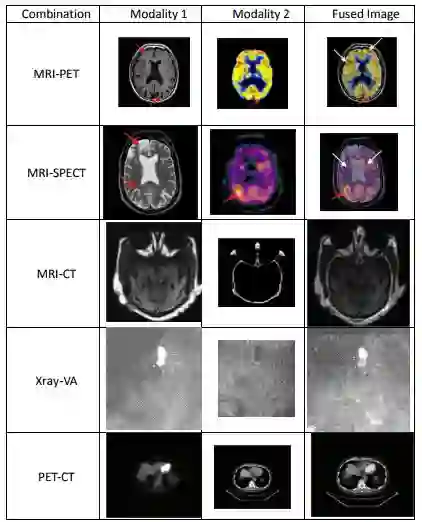

4、图像融合

图像融合的主要目的是通过对多幅图像间的冗余数据的处理来提高图像的可读性,对多幅图像间的互补信息的处理来提高图像的清晰度。多模态医学图像的融合把有价值的生理功能信息与精确的解剖结构结合在一起,可以为临床提供更加全面和准确的资料[23]。融合图像的创建分为图像数据的融合与融合图像的显示两部分来完成。目前,图像数据融合主要有以像素为基础的方法和以图像特征为基础的方法。前者是对图像进行逐点处理,把两幅图像对应像素点的灰度值进行加权求和、灰度取大或者灰度取小等操作,算法实现比较简单,不过实现效果和效率都相对较差,融合后图像会出现一定程度的模糊。后者要对图像进行特征提取、目标分割等处理,用到的算法原理复杂,但是实现效果却比较理想。融合图像的显示常用的有伪彩色显示法、断层显示法和三维显示法等。伪彩色显示一般以某个图像为基准,用灰度色阶显示,另一幅图像叠加在基准图像上,用彩色色阶显示。断层显示法常用于某些特定图像,可以将融合后的三维数据以横断面、冠状面和矢状面断层图像同步地显示,便于观察者进行诊断。三维显示法是将融合后数据以三维图像的形式显示,使观察者可更直观地观察病灶的空间解剖位置,这在外科手术设计和放疗计划制定中有重要意义。

图12 多模态医学图像融合的例子。使用特定图像融合技术的模态1与模态2的组合可以使医学诊断和评估改进